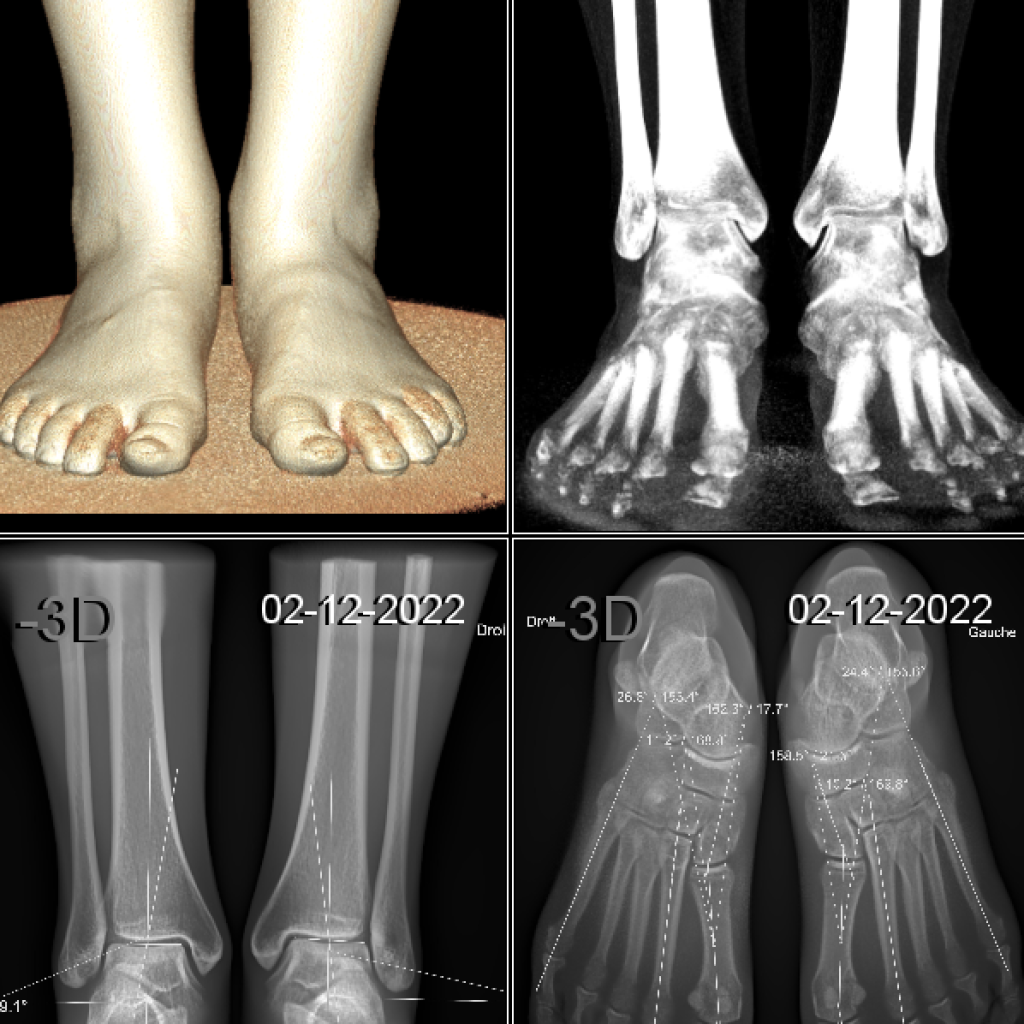

Il s’agit d’un appareil type cone beam permettant d’étudier en position débout, comme un scanner, les pieds, les chevilles et les genoux avec une très faible irradiation du patient comparé à un scanner conventionnel.

Il se destine aux pathologies liées aux troubles posturaux, aux douleurs des avants et arrières pieds.

Le patient est debout et l’appareil tourne autour de ses pieds sans entrer en contact avec lui.

Il suffit de moins d’une minute pour obtenir une acquisition volumique 3D des pieds et des chevilles.